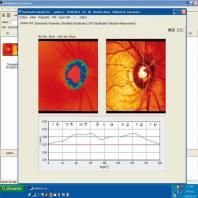

- eFig. 9-3 - Relevé d'écran d'accueil HRT